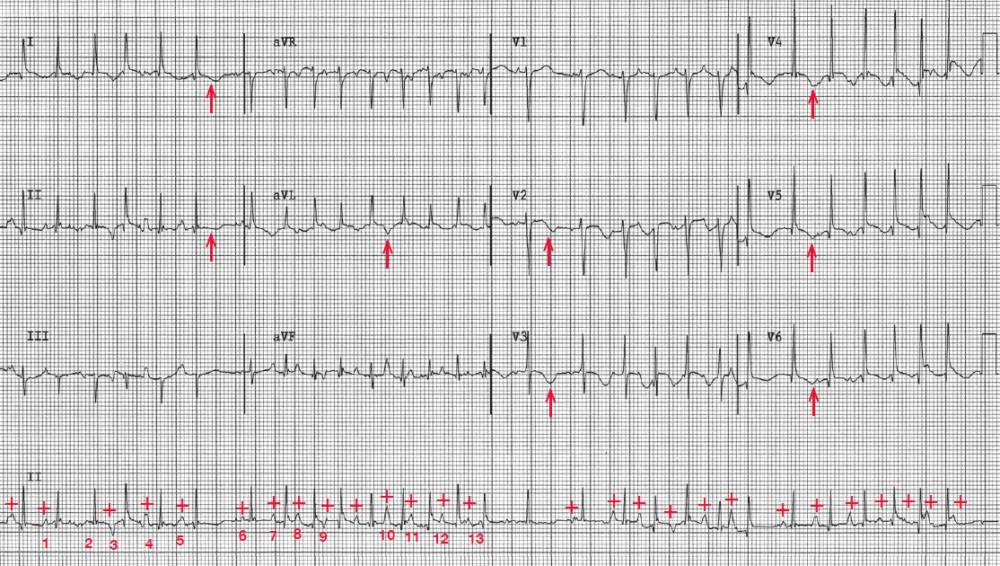

The rhythm is irregularly irregular at an average rate of 168 bpm. There are only three supraventricular rhythms that are irregularly irregular:

There is a P wave (+) before each QRS complex, but there are multiple (three or more) P-wave morphologies with no P-wave morphology being dominant. Therefore, this is multifocal atrial tachycardia and not atrial fibrillation. There are diffuse ST-T wave changes (↑) noted.